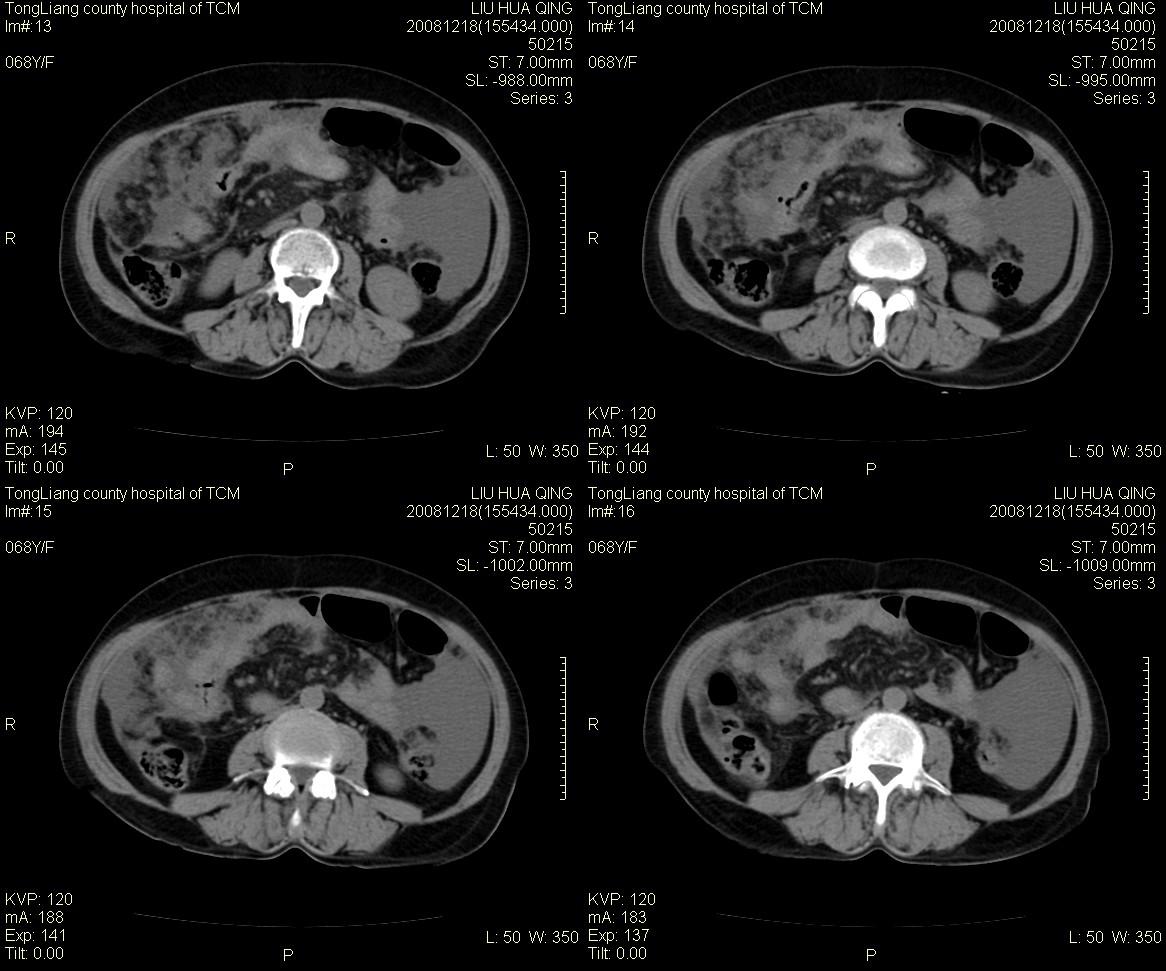

从网上找来的结核性腹膜炎,与这个病例有些共同点。请各位战友比较一下。